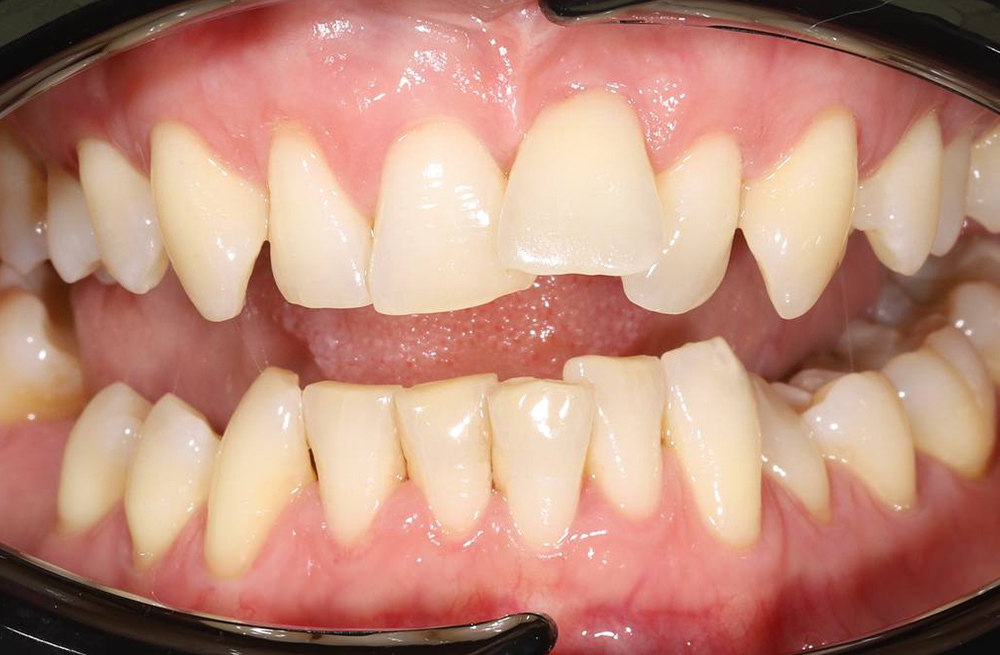

Исправление неровных зубов и недостатка места для зубов у подростка